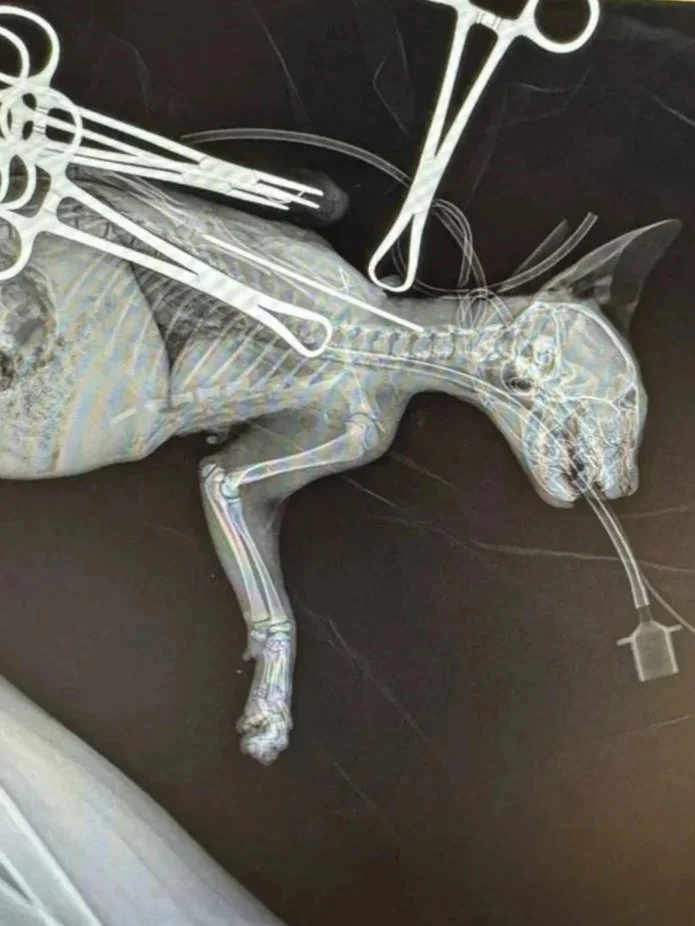

Moose was recently surrendered into LAWS’ care after a heartbreaking accident at home. This curious little kitten took a tumble from a three-level bunk bed, leaving him with a severely broken leg and in need of urgent medical attention.

Thanks to the incredible generosity of Orphan Kitten Club and Kitten Lady, Moose received a lifesaving medical grant that fully covered his surgery costs. Our wonderful partners at Gem City Veterinary placed a pin through his fractured leg, and Moose has been making an amazing recovery ever since!